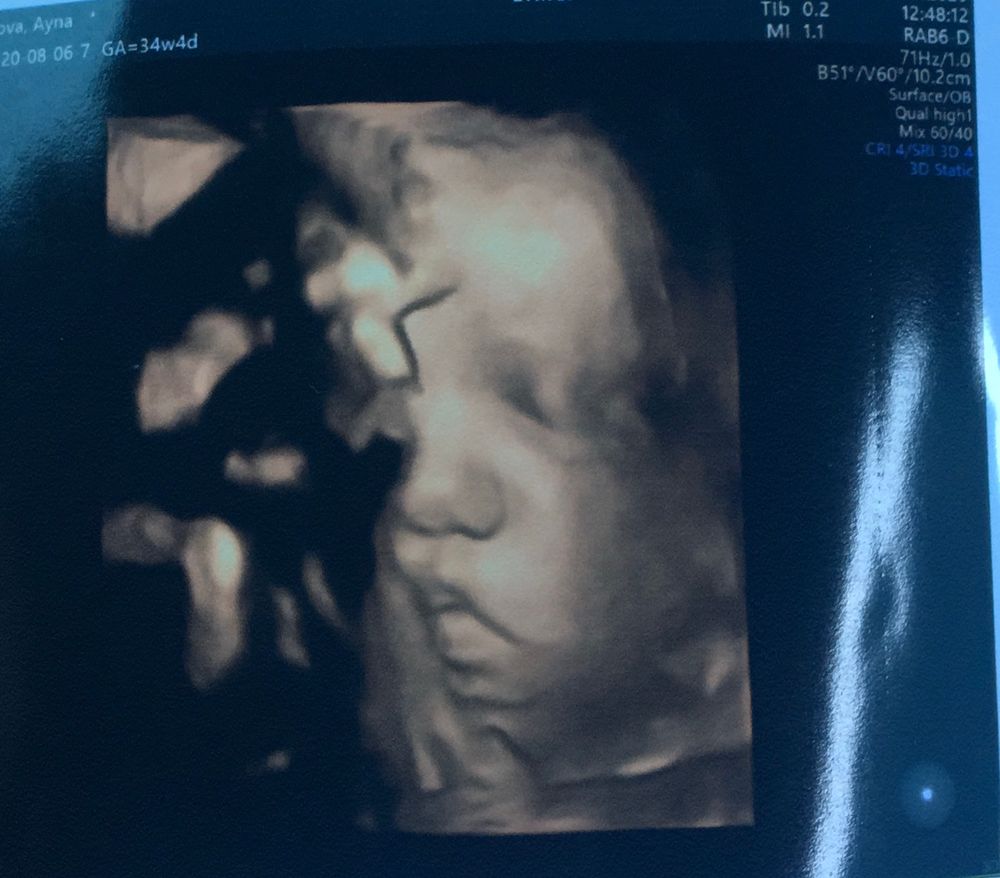

ну все я почти на финишной прямой. Тут девочек, которых наблюдала, отстрелялись многие. Теперь жду своей участи;) срок уже 36.4; плановое кесерево стоит на 1.09; ждемс. Но уже начало болеть низ живота, как перед мес., пошла к врачу; сказала рано, давай на папаверине лежи, жди. Режим ждуна активирован. Ещё плюс с анестезиологом поговорили, сказала раз я на клексане будет наркоз общий. Я так не хотела его(с 1ым Настродалась) первый у меня маловесный был 2900. Эта принцесса на 34,4 нед была 2500.(интересно какой родится)